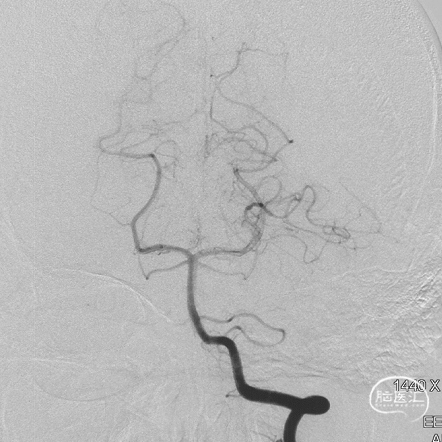

术后三个月造影复查,双侧颈内动脉、颈外动脉造影均未见静脉早显,DAVF治愈。